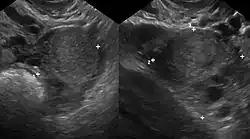

Ultrazvuk

Vaginální ultrazvuk lze použít k diagnostice endometriózy nebo k lokalizaci endometriomu před operací. Může pomoci určit rozsah onemocnění u jedinců s klinickým podezřením na endometriózu. Vaginální ultrazvuk je levný, snadno dostupný, nemá žádné kontraindikace a nevyžaduje žádnou přípravu.[61] Rozšířením ultrazvukového vyšetření do zadního a předního pánevního prostoru je sonografista schopen vyhodnotit strukturální mobilitu a vyhledat hluboké infiltrující endometriotické uzly. Zlepšená ultrazvuková detekce hluboké infiltrující endometriózy by mohla snížit počet diagnostických laparoskopií a také by mohla pomoci při léčbě onemocnění a zlepšit kvalitu života pacientky.[62]

Je velmi obtížné určit celkový počet žen s endometriózou, protože potvrzení diagnózy vyžaduje chirurgickou laparoskopickou operaci. Kritéria, která se běžně používají ke stanovení diagnózy, zahrnují bolest v pánevní oblasti, neplodnost, chirurgické potvrzení a v některých případech zobrazení magnetickou rezonancí. Ultrazvuk může identifikovat velké shluky tkáně jako potenciální ložiska endometriózy a cysty na vaječnících, ale nefunguje u všech pacientek, zvláště u těch s menšími povrchovými ložisky.[17]